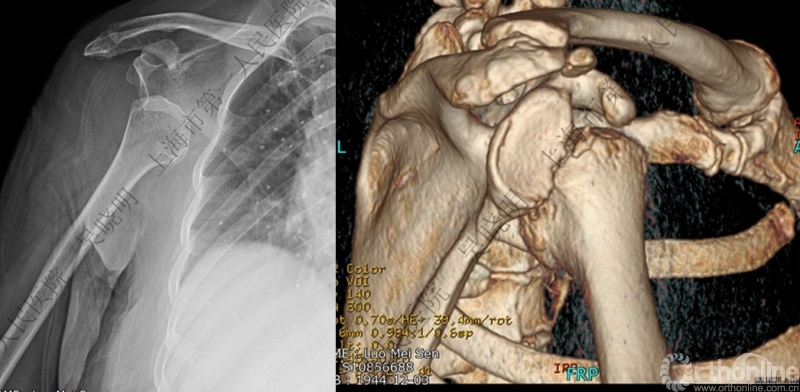

X线看不清骨折线,三维CT也看不清

老年性肩关节脱位伴大结节骨折:与肩胛盂和肱骨头撞击有关

骨折线可以延伸到肱骨头

必要时进一步CT检查

必需时进一步急诊CT检查